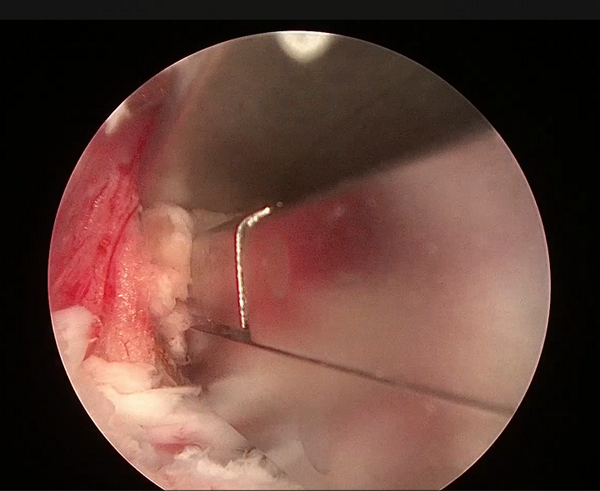

髓核摘除前后对比

切除后黄韧带和椎间盘髓核组织

患者接受手术治疗,术中仅通过两个长约0.5cm及1cm的手术切口,置入脊柱内镜及操作器械,逐步扩大“狭窄的椎管”并顺利摘除“脱出的椎间盘组织”,解除神经受压情况。

5.摘除髓核